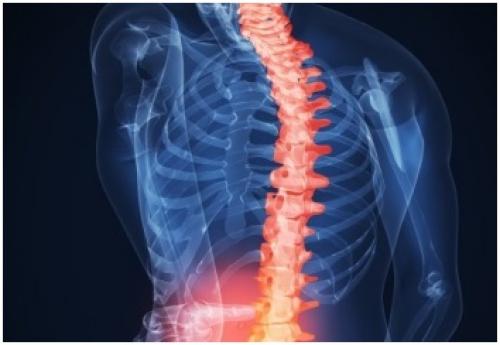

Уколы для восстановления хрящевой ткани позвоночника. Как восстановить хрящевую ткань позвоночника?

Восстановление хрящевой ткани позвоночника возможно за счет приема хондропротекторов, витаминов, гормональных средств. Плюс к медикаментам идет нормализация питания и полный отказ от табакокурения и алкоголя. Начинать лечение не рекомендуется без ведома специалиста.

Как восстановить хрящевую ткань позвоночника?

Как обновить хрящ? При умеренных изменениях в хрящевой ткани позвоночника, специалисты назначают лекарственные препараты, витамины, рекомендуют наладить питание.